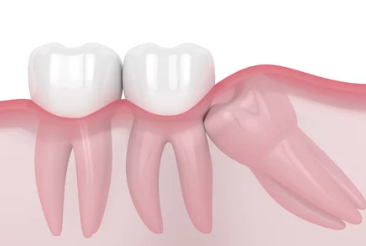

매복 사랑니의 의미

사랑니가 잇몸 아래에서 정상적으로 자라지 못하고, 잇몸 안이나 다른 치아에 눌려 비정상적인 방향으로 자라는 상태를 매복 사랑니라고 합니다. 매복의 정도는 다음과 같이 나뉩니다:

- 부분 매복: 사랑니 일부가 잇몸 밖으로 나와 있는 상태.

- 완전 매복: 사랑니가 완전히 잇몸 아래에 매복된 상태.